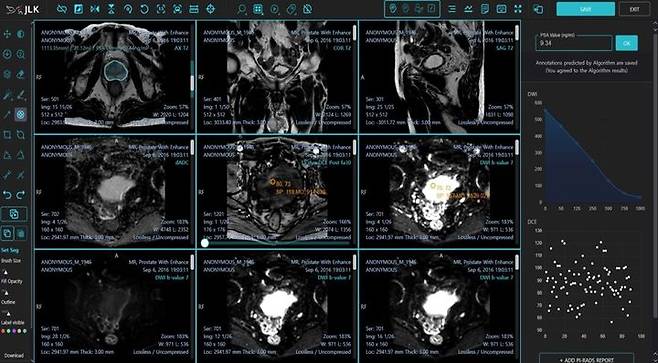

제이엘케이는 인공지능(AI) 전립선암 진단 솔루션 '메디허브 프로스테이트(MEDIHUB Prostate)'가 미국 식품의약국(FDA) 510(k) 승인을 획득했다고 24일 밝혔다.

[서울=뉴시스] 배요한 기자 = 제이엘케이는 인공지능(AI) 전립선암 진단 솔루션 '메디허브 프로스테이트(MEDIHUB Prostate)'가 미국 식품의약국(FDA) 510(k) 승인을 획득했다고 24일 밝혔다.

이번 FDA에서 승인된 MEDIHUB Prostate는 제이엘케이가 서울아산병원, 미국 미주리 대학과의 임상시험으로 개발한 전립선암진단 AI 솔루션이다.

전립선암의 진단과 추적에는 다중 매개변수(Multiparametric) 전립선 MR 영상이 활용되며, 질병에 대한 조직학적 이해 및 MR 영상에 대한 많은 경험이 필요하다.

또 판독의사들의 숙련도에 따라 진단의 난이도가 있는 질환으로 세계적으로 인증된 바이오 마커인 PIRADS(Prostate Imaging Reporting and Data System) 점수를 표준화해 사용하고 있다.

MEDIHUB Prostate는 인공지능을 활용해 Multiparametric 전립선 MR 영상을 복합적으로 분석하고 AI가 PIRADS 진단 및 PSA(전립선 특이 항원) 진단 등의 전립선 진단에 필요한 모든 데이터를 제공한다.